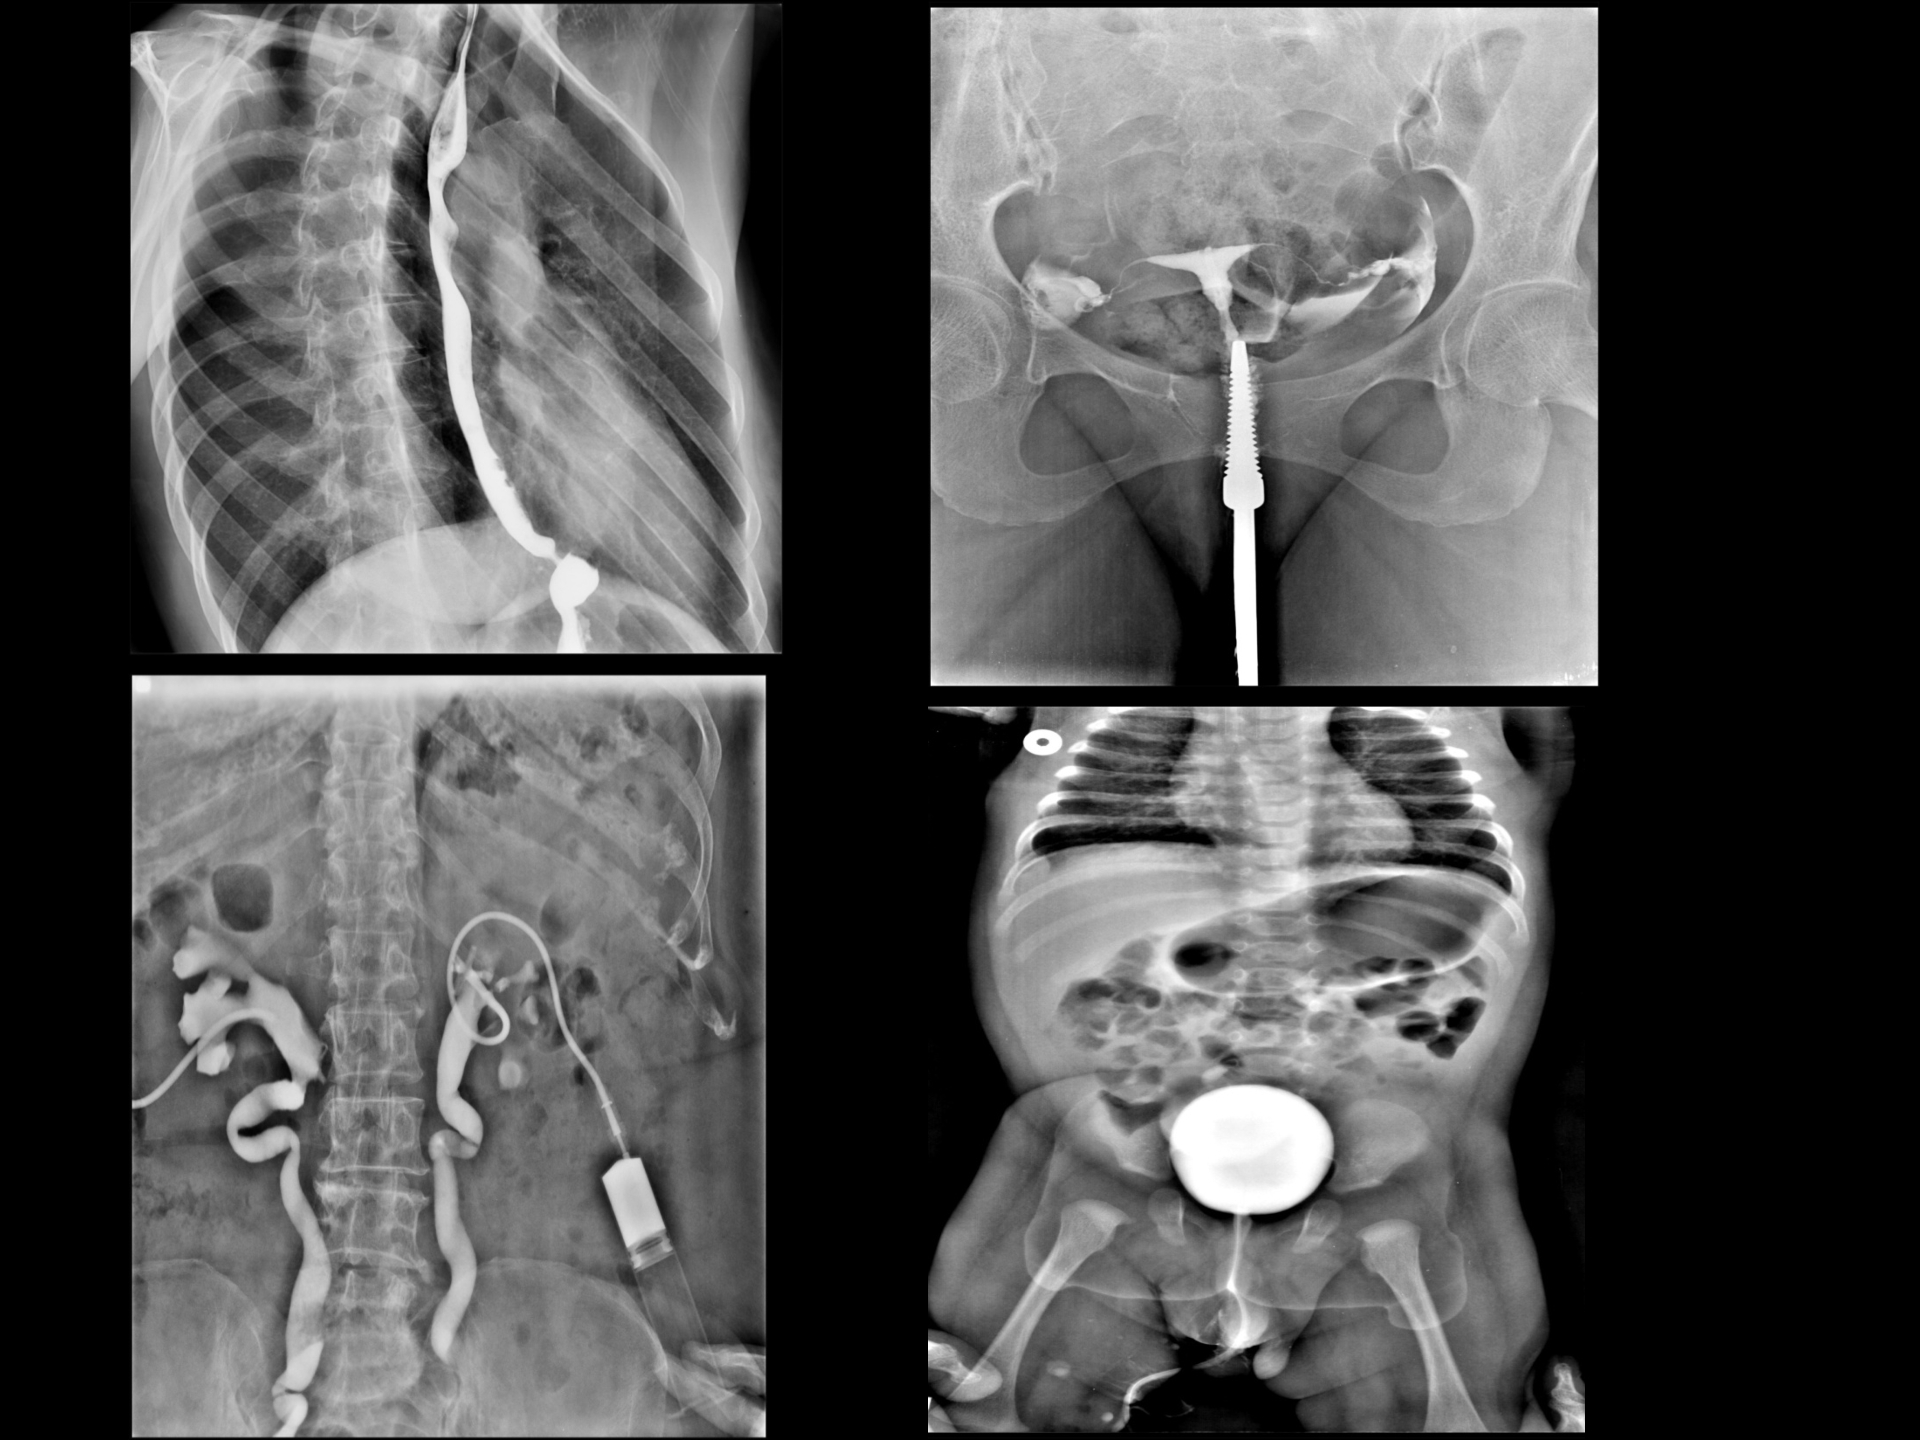

Fully automatic X-ray machine is having DR (Direct Radiography) system.

Advanced DRF technique designed for Digital radiography as well as Full-length Scanogram and Live Fluoroscopy.